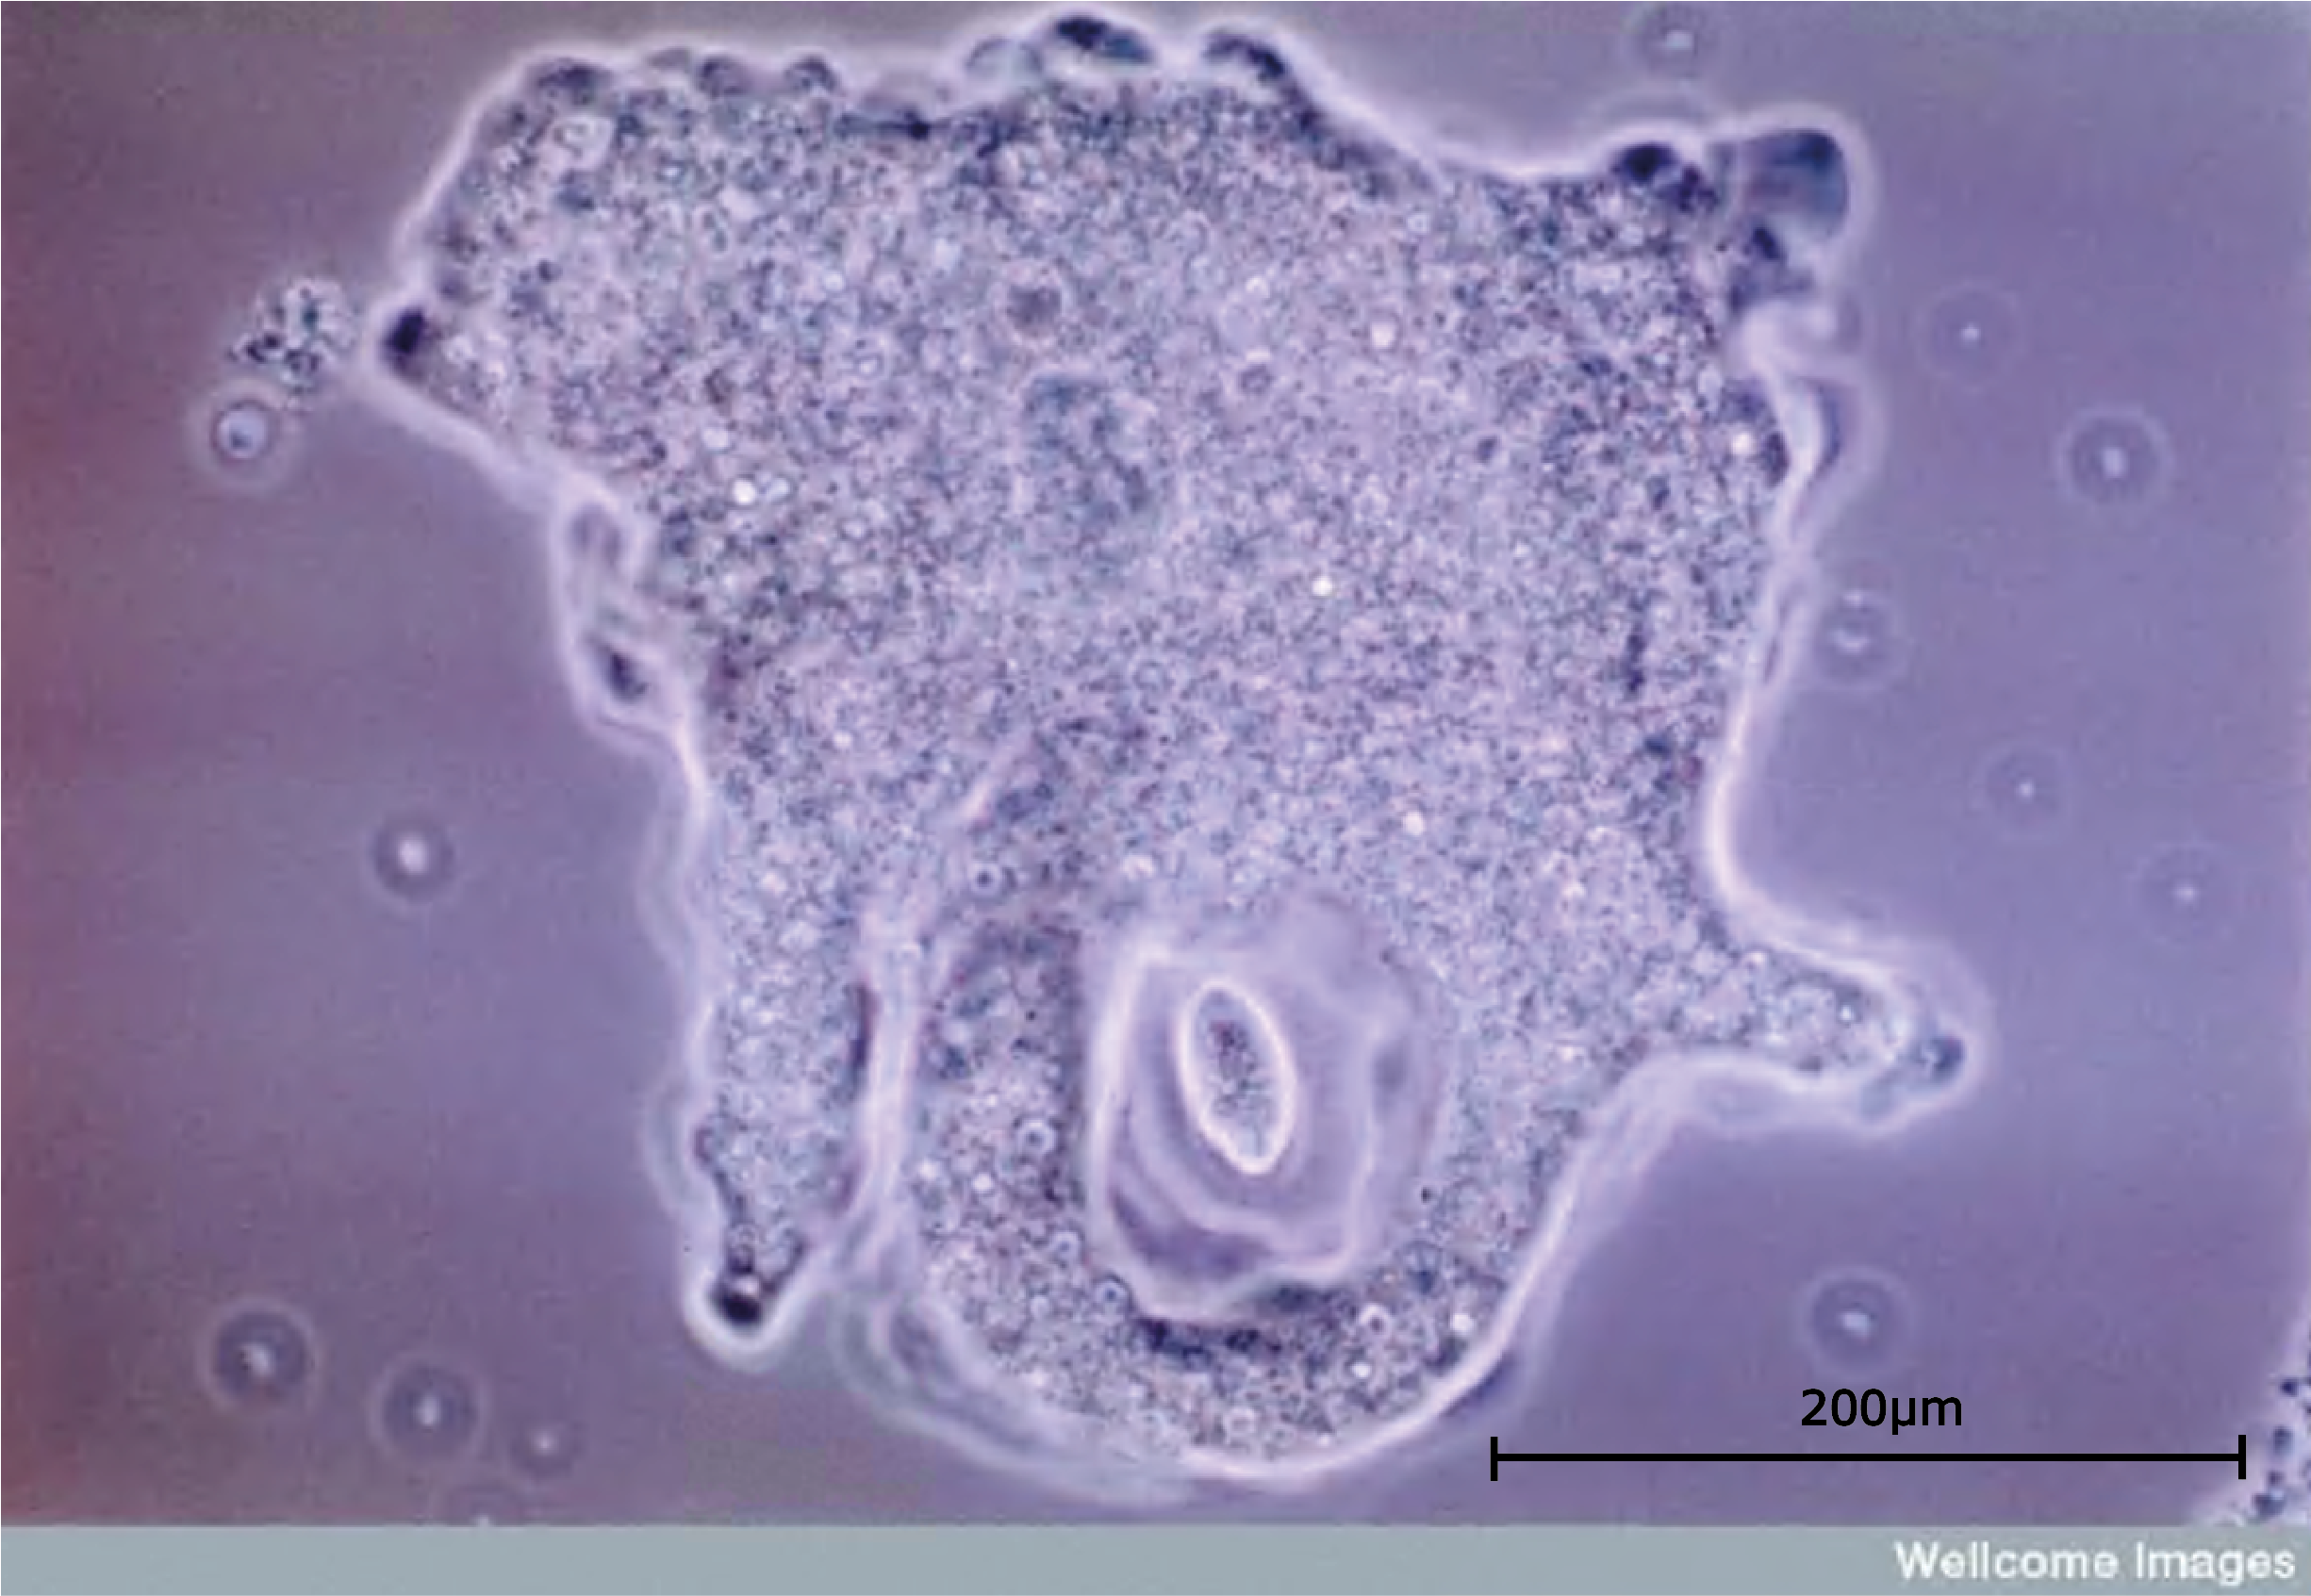

The protista consist of unicellular eukaryotic organisms which have a variety of methods of nutrition and reproduction. These single celled organisms come in an enormous range of shapes and lifestyles: from amoeba to diatoms, including plant-like cells that swim, animal-like cells that cannot move, cells that are shaped like bells or fans or shells - some may even be grouped into colonies. Within the protista are organisms which make up the greater part of the plankton of the oceans, and a few which cause some of the most serious diseases to affect the human race. In some ways the kingdom of the protista contains all the organisms which scientists are not able to classify into one of the other kingdoms.

Amoeba Scale